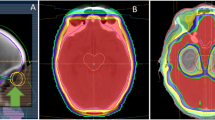

The origins and extent of tumor immunosurveillance in the CNS are not fully defined. Preclinical evidence has shown that APCs are present in the brain parenchyma and ultimately drain into cervical nodes of the neck, where they can present tumor antigens to circulating T cells to generate a systemic immune response. Recently, discovery of draining lymphatics along the dura has provided more insight into this pathway. Intraparenchymal cerebrospinal fluid (CSF) carrying cells and antigens from the brain tissue flow out to the subarachnoid reservoirs of CSF [18]. Enriched by these substrates, the CSF diffuses into lymphatic vessels, which run in parallel along the dura. The lymph fluid follows this path along the sagittal sinus, which ultimately reaches deep cervical lymph nodes to interface with the peripheral immune system (Fig. 25.1). Overall, the brain has a unique immune microenvironment. Its resident immune cell population, blood-brain barrier, and distinct lymph drainage channels add to the complexity of strategically targeting metastatic CNS tumors with immunotherapy.

Histologic evaluation has revealed the presence of lymphatic vessels in the meninges of the brain. They line the dural sinuses and serve as an interface with cerebrospinal fluid carrying cells and soluble particles from the brain parenchyma. The brain lymphatics are a channel for immune cells and fluids to drain to the deep cervical nodes where they can interact with the peripheral immune system